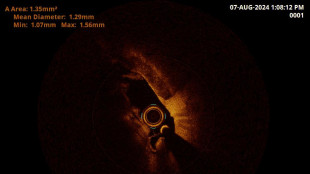

L'Ia contro le malattie coronariche, uno studio a Torino

Permetterà di decidere se procedere con un'angioplastica

Ospedale Grosseto vede arteria vertebrale in 3D con nuovo metodo

Diagnosi unica in Italia dopo l' esperienza sulle coronarie